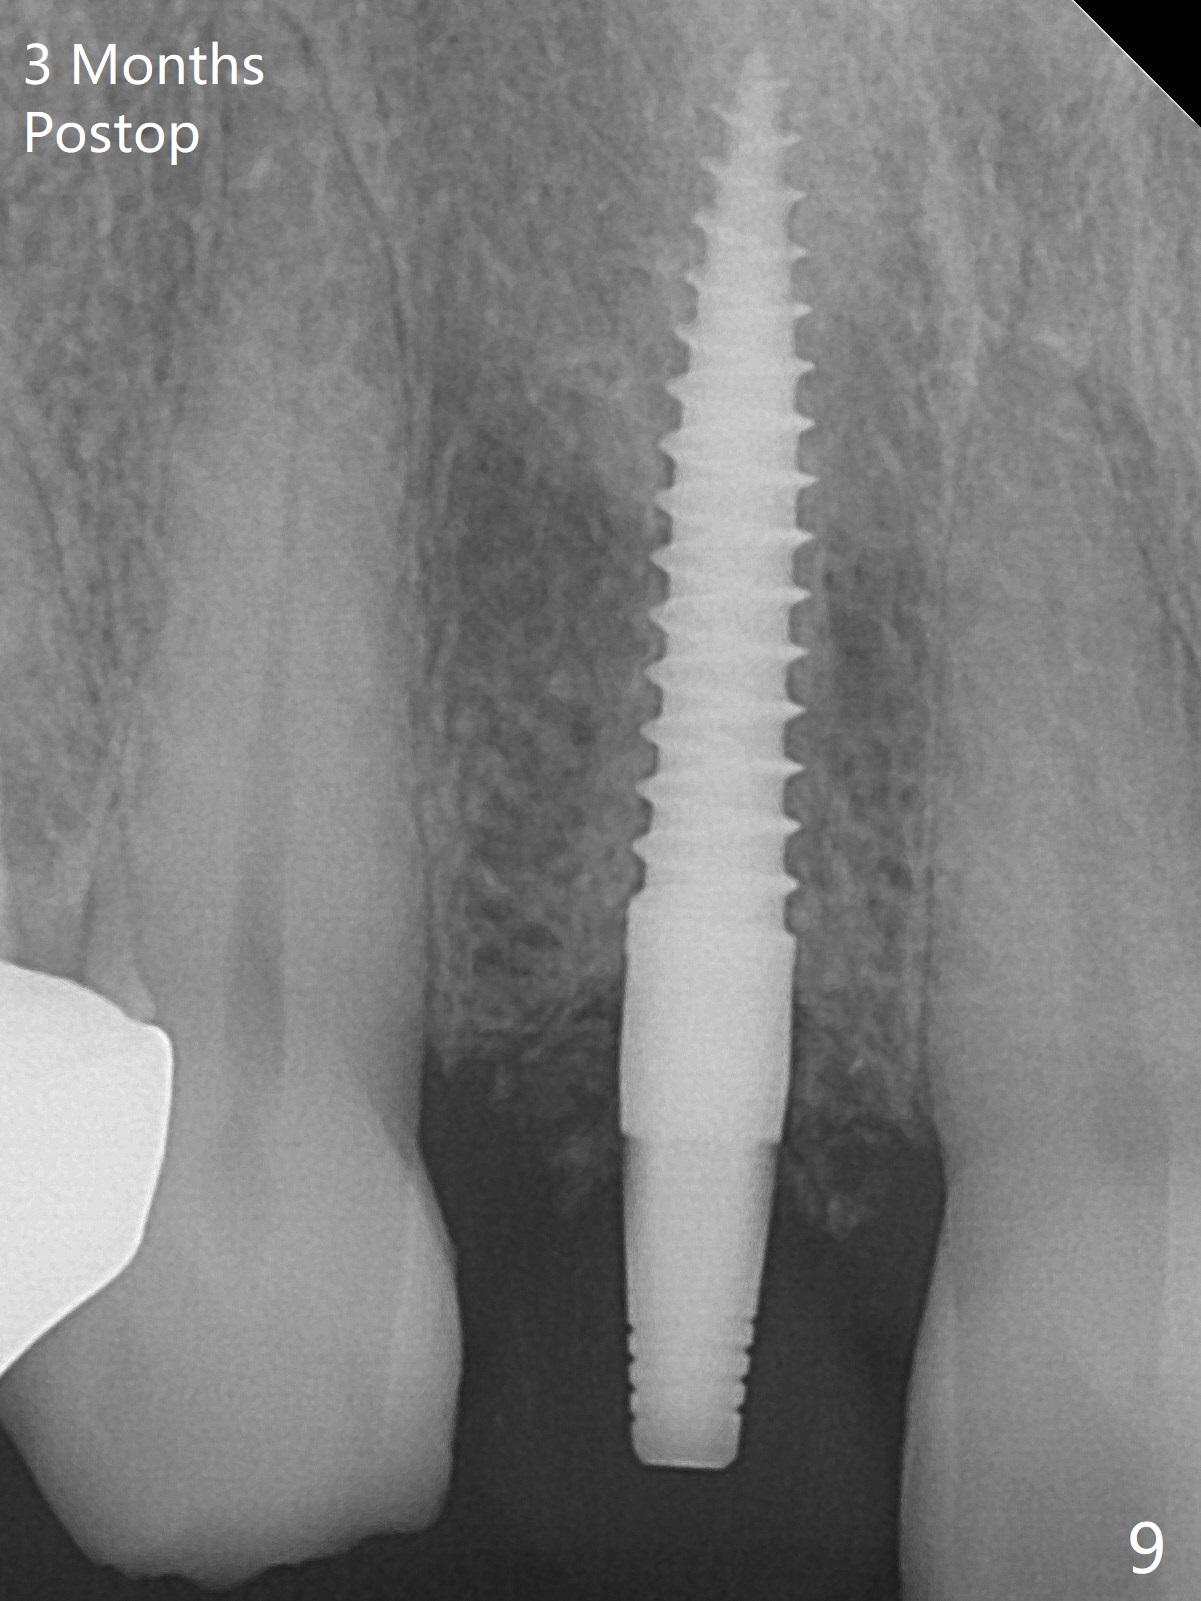

The rebonded crown at #7 debonds in a few days. There is deep anterior overbite and buccal concavity (Fig.1 *). The equigingival fracture (Fig.1,2) seems difficult to restore considering lack of posterior support (lower RPD in Fig.1). Buccal shield is tried in spite of the long root. It is not easy to tell whether the infected apex is removed due to the deep socket. In fact the apical buccal plate perforates because of use of surgical handpiece. Finally the buccal shied is removed. PA confirms the retained apex (Fig.3 *). The initial osteotomy with 1.5 mm drill in place is off trajectory (Fig.4). After adjustment of the trajectory of osteotomy (Fig.5), a 3x16(2) mm 1-piece implant is placed within normal limit (10-15 Ncm, Fig.6)). In fact bone graft is placed before (Fig.6,7 arrowhead; to repair apical buccal plate perforation) and after (Fig.6 *) implantation. The gingiva (including papillae) remains normal around the provisional 3 months postop (Fig.8). The bone graft becomes more organized 3 months postop (Fig.9), continues to do so 4.5 months postop (Fig.10) and becomes dense coronally 9 months post cementation (Fig.11: *).